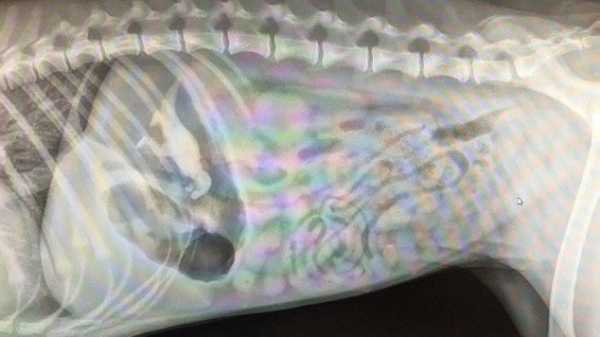

7-місячний лабрадор, що проковтнув динозавра

Звичайно ж іграшкового